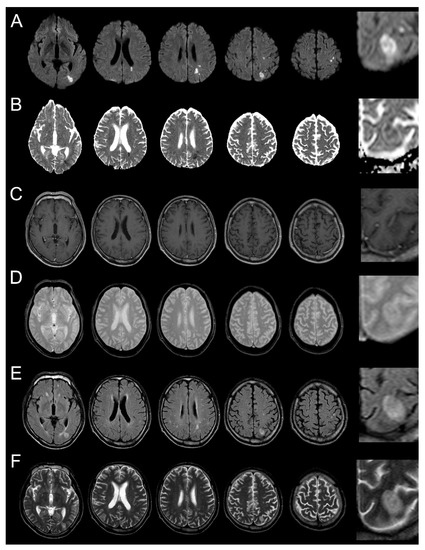

Figure 1.

Brain MRI was performed 2 days after symptom onset. (A): diffusion-weighted magnetic resonance imaging (MRI); (B): apparent diffusion coefficient map (ADC); (C): contrast enhanced T1-weighted MRI; (D): T2 *-weighted MRI; (E): fluid-attenuated inversion recovery (FLAIR); (F): T2-weighted MRI). Multiple lesions can be seen in the border area between the middle cerebral artery and posterior cerebral artery in the left hemisphere. High signal intensity lesions on diffusion-weighted MRI and their corresponding low-signal lesions on the ADC, without enhancement on contrast-enhanced T1-weighted MRI and without low signal on T2 *-weighted MRI, are seen. T2-weighted MRI shows a high signal lesion with subtle low signal in the center of the ovoid-shaped dominant peripheral lesion. Figures in the right column are magnified regions of interest from the images of the lesion marked (*).